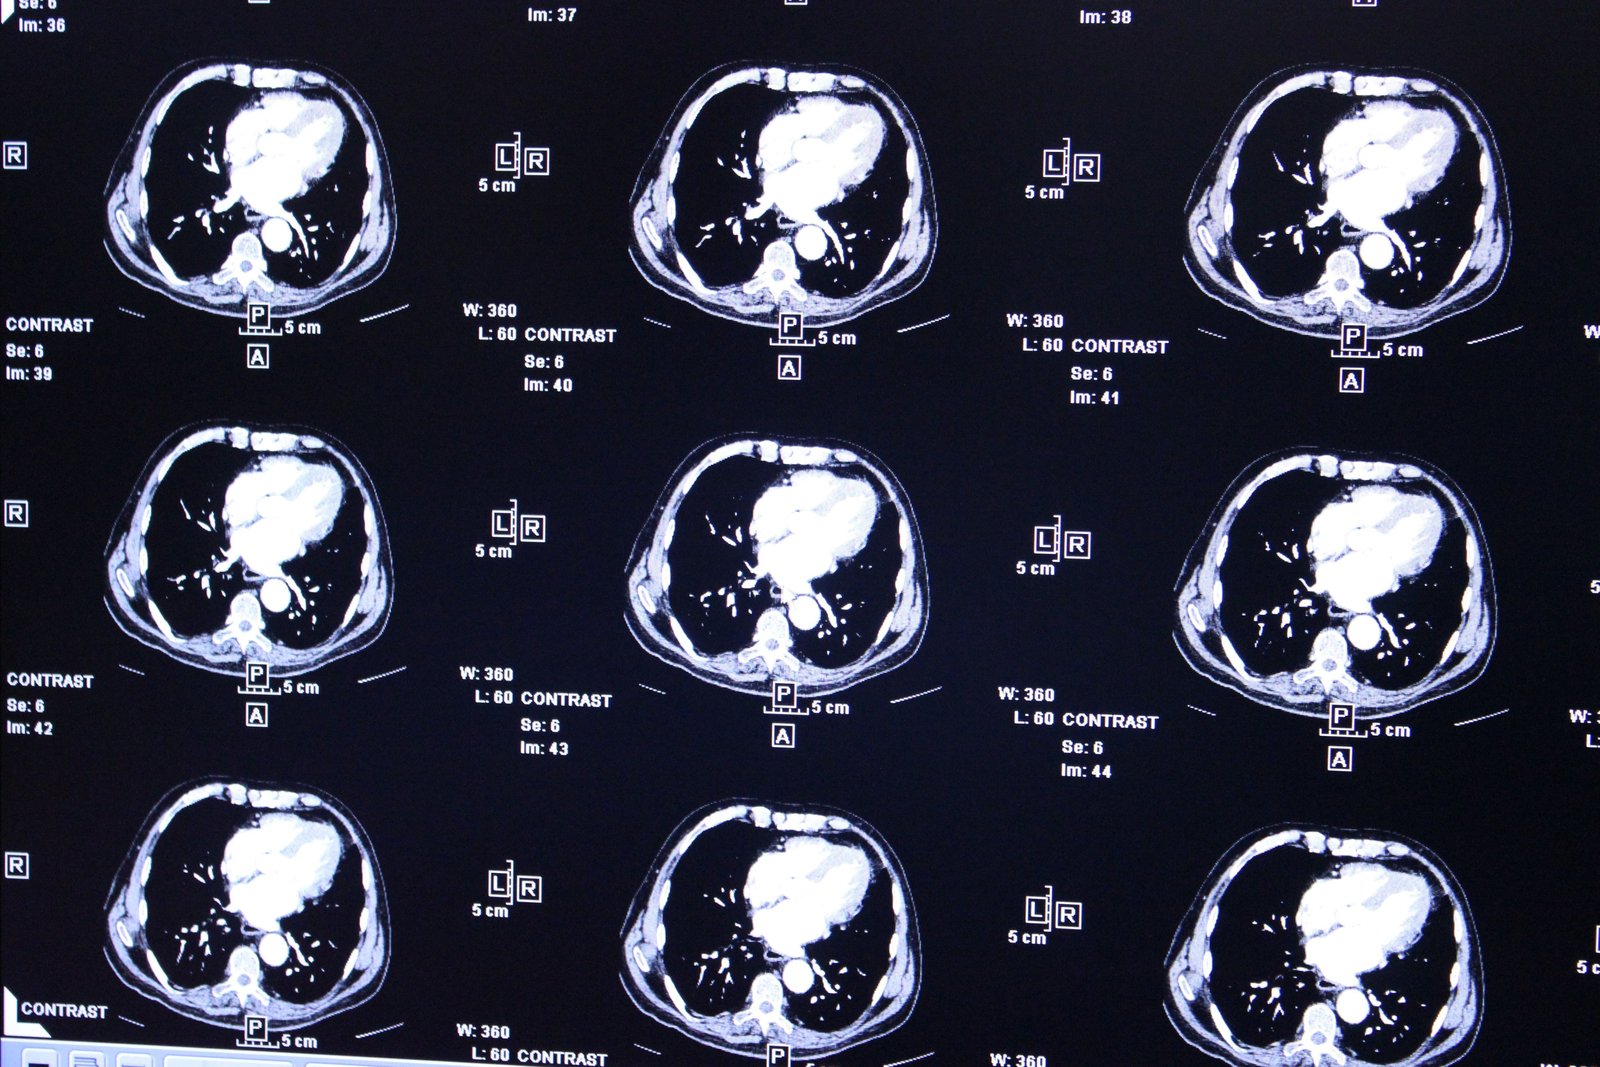

Las resonancias magnéticas cerebrales de los seis pacientes inscritos en el ensayo mostraron reducciones rápidas del tumor que ocurrieron dentro de uno o dos días después del tratamiento. En algunos casos, esas reducciones han continuado durante meses, dijo el equipo de la Universidad de Pensilvania.

También idearon una forma de garantizar que las células CAR-T llegaran directamente al cerebro. En lugar de administrarlos a través de un goteo intravenoso, como es habitual, el equipo los inyectó en el líquido cefalorraquídeo de cada paciente, que viaja directamente al cerebro. La estrategia pareció funcionar: las resonancias magnéticas tomadas solo 24 y 48 horas después de la administración de CAR-T mostraron una notable reducción de los tumores.